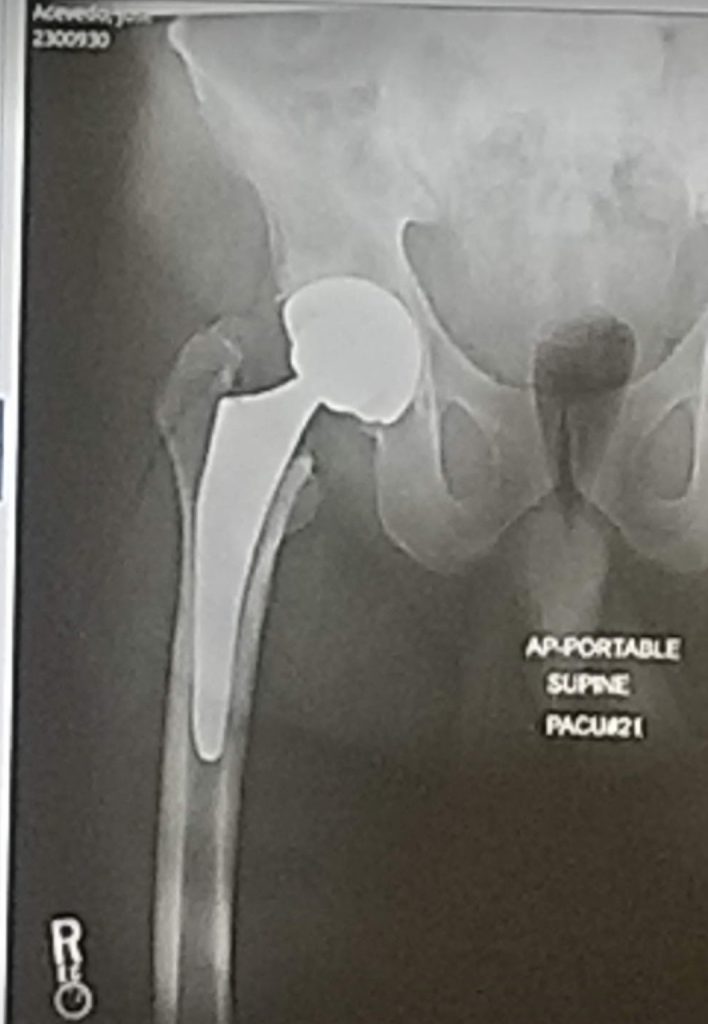

My name is Jose Acevedo from the Bronx, NY. For the past 10 years, my life was a living hell. My right hip was always in pain. I developed hip arthritis and I was walking bone-on-bone because there was no cartilage left inside. No type of medication helped my condition. Injections, creams or pills did not ease my pain. My life was very limited, and my physical activities were non-existent. Things were so bad I needed help to put on my socks and shoes. The pain was so excruciating that it made me walked with a limp. People was always asking what was wrong with me. I got tired of living like that, so I mustered up some courage and make a phone call to HSS. I made an appointment with Dr. DiFelice because some family members and friends had procedures done with him in the past and they were doing fine now. The moment I walked into his office I felt comfortable with the care and professionalism. Dr. DiFelice explained to me why I was in so much pain and limping. He told me the pros and cons of surgery but he also told me something super important. He said hip replacement was the most predictable surgery in history and if he needed surgery this was the one he would like. Right then and there I made a decision to have surgery. I had surgery on 3/4/21. Since my surgery my life improved. There is no more pain, no more limp, and no more meds. I regret taking so long to do this procedure. It's been 7 weeks since my surgery and I just got back from a long needed vacation from the Dominican Republic. My wife and I had the best time of our lives because I was able to walk with out stopping and do all the activities couples do on vacation. So to conclude, if you or anyone you know is in need of a total hip replacement do it. Don't let fear of the unknown stop you. You don't have to live in pain, there is a solution and you will not regret it. Recovery is not bad or painful and you will feel just like I feel. Like a new person. I thank Dr. DiFelice and his team for what they done for me. HSS is the most amazing hospital I have ever been in. They really know how to care for a patient. They are the best of what they do.